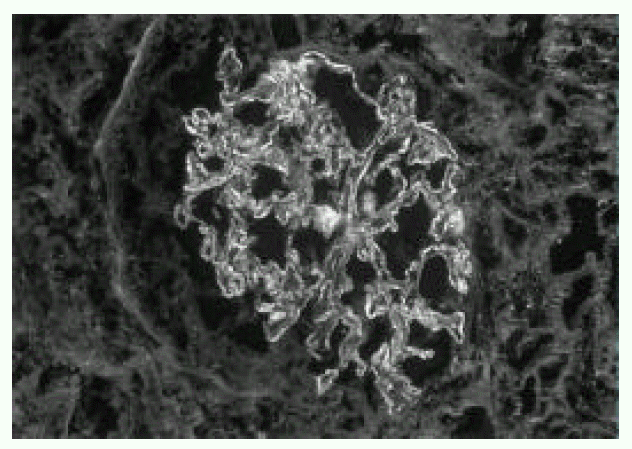

Figure 1.

Abdominal CT showing 7×5 cm sized multiple separated lower density lesion in medial segment of left hepatic lobe.

A 66-year-old man was admitted to Keimyung University Hospital because of decreased urine output and right upper quadrant pain. Seven years earlier, he had a Whipple’s operation for obstructive jaundice due to Ampulla of Vater cancer. At that time, the pathology report showed a moderately differentiated adenocarcinoma and biopsies of the regional lymph nodes showed no evidence of metastasis. At that time, renal function was normal and the urine contained no proteins or red cells. Two weeks before admission, the patient developed right upper quadrant dull pain, nausea, anorexia, myalgia, chills and fever. Four days prior to admission, he noticed gross hematuria, marked decrease in urine output and edema in lower extremities. On admission, his body temperature was 36.4°C and blood pressure was 110/60 mmHg. Daily urine output ranged 800–1200 mL. Face was puffy. He did not have icterus. His conjunctivae was slight anemic and revealed several petechial hemorrhages. Auscultation of the lung revealed bilateral basilar rales. No murmurs or frictions were heard. The liver was enlarged and tender. There was no splenomegaly or rash. There was marked costovertebral angle enderness. here was mild pretibial edema. Laboratory data on admission showed WBC 34,600/mm3, hemoglobin 8.3 g/dL, platelet count 95,000/mm3, BUN 16.4 mmol/L, serum creatinine 985,6 μmol/L, cholesterol 118 mg/dL, total bilirubin 3.4 mg/L, alkaline phosphatase 270 IU/L, SGPT 18 IU/L, and serum albumin 2.0 g/dL and creatinine clearance 2.5 ml/min. Urinalysis showed specific gravity 1.020, protein 2+, and urinary sediment containg two granular casts, many red blood cells and 10 white blood cells/HPF. The 24-hour urinary protein excretion was 2.4 gm and FENa was 1.7%. C3 level was 0.67 g/L (normal range: 0.8–1.2 g/L) and C4 level was 0.46 g/L (normal range: 0.2–2.5 g/L). Cryoglobulin was absent. The tests for hepatitis B and C, antinuclear antibody and rheumatoid factor were negative. Chest radiographs demonstrated bilateral perihilar pulmonary congestions. On admission, he was afebrile. He had obvious pulmonary edema as well as peripheral edema. Immediate hemodialysis resulted in a weight loss of 2 kg and respiratory improvement. Ultrasonographic examination of liver showed ill marginated cystic mass in left lobe. Computed tomography (CT) of the abdomen demonstrated 7×5cm sized multiple septated lower density lesions in medial segment of left lobe of the liver (Figure 1). Numerous blood cultures were negative. Initially the patient was treated with diuretics, albumin infusions and antibiotics (sulbactam/cefoperazone and aztreonam). On the 15th day, percutaneous needle biopsy of the kidney was performed. Light microscopy showed 17 glomeruli with two global sclerosis. The glomeruli showed endo-and extracapillary proliferation (Figure 2), with cellular crescents involving 25% of the glomeruli. The interstitium showed diffuse edema and no tubular necrosis. Immunofluorescent examination showed a diffuse granular staining with anti-IgG and anti-C3 along the capillary wall, and no staining with anti-IgM or anti-IgA (Figure 3). Needle aspiration of the liver was performed on the 19th hospital day, with the drainage of greenish pus material. Culture of the liver aspirates later grew Pseudomonas aeruginosa. Ticarcillin was given. The patient improved substantially. The levels of BUN and serum creatinine declined progressively and stabilized at 5.7 mmol/L and 176 μmol/L, respectively, by the 25th hospital day. One month after admission, the laboratory findings were : BUN 5.5 mmol/L, serum creatinine 176 μmol/L, hemoglobin 8.1g/dL. WBC 5,430/mm3 and platelet count 208,000/mm3. The 24-hour urinary protein excretion was 4.4 g/day. Follow-up CT showed almost complete resolution of previous abscess in the liver. He was discharged on the 40th hospital day with the serum creatinine level of 167 μmol/L.